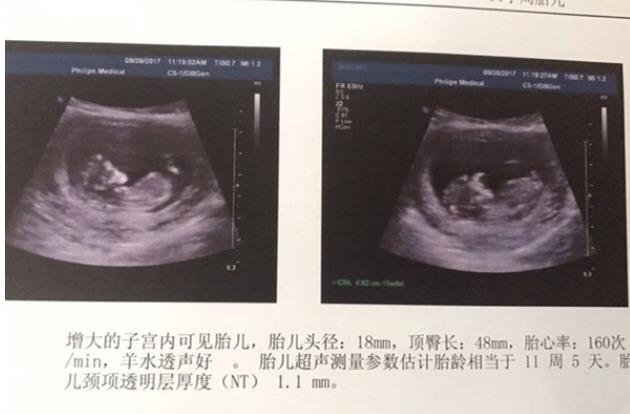

山西红房子医院内部护士前胎